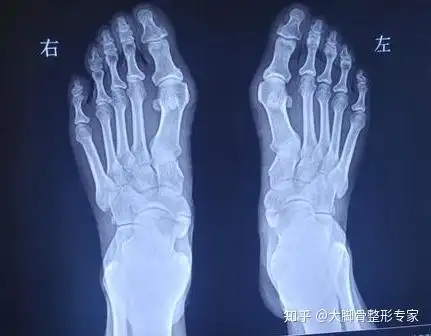

如果大脚骨手术不是削掉骨头那么到底应该怎么做才好呢